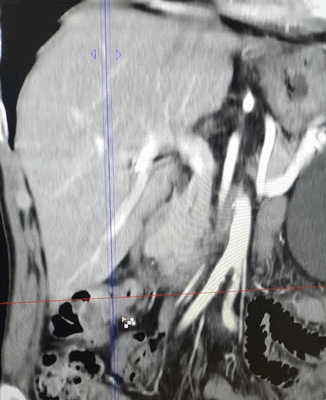

- Дополнительные методы. Для обнаружения очагов в лимфоузлах и отдаленных органах осуществляют КТ и УЗИ брюшной полости.

КТ ОБП/ЗП. Циркулярная мягкотканная опухоль (красная стрелка) стенки поперечной ободочной кишки, значительно суживающая ее просвет.